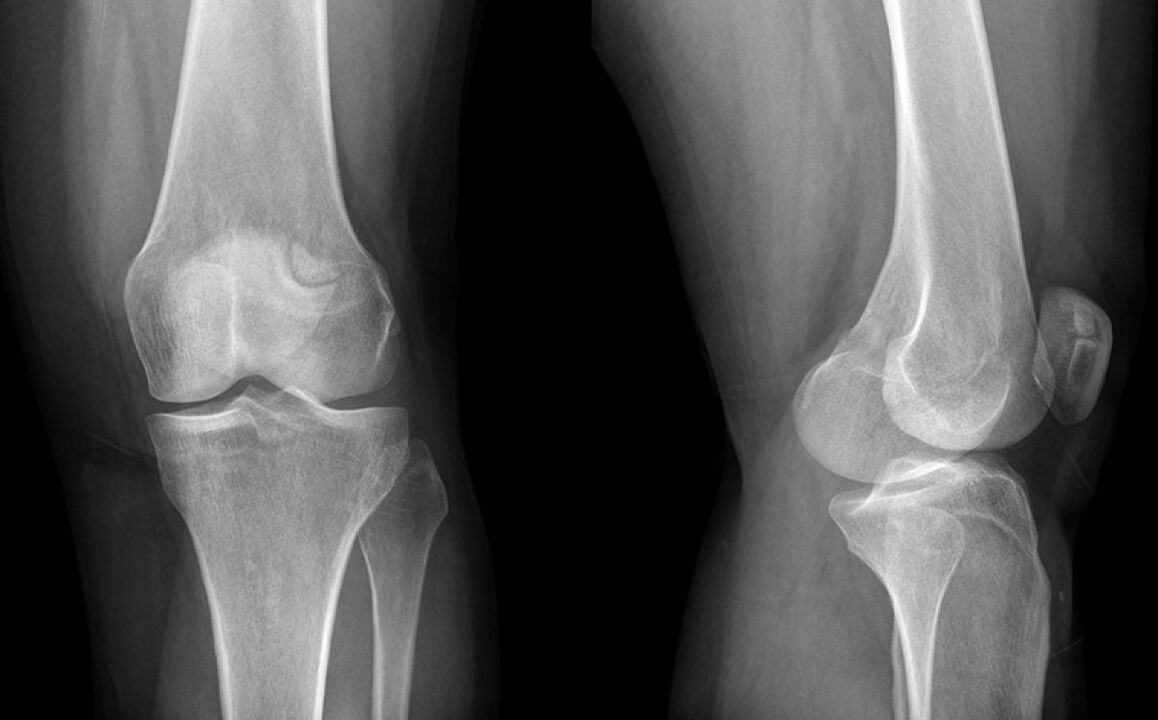

A térd három hétig fáj. Végül olyan orvoshoz mentem, aki gyanította a meniszkusz károsodását és elküldte egy X -Gray -t. A diagnózis a térdízület artrózisának kezdeti stádiuma.